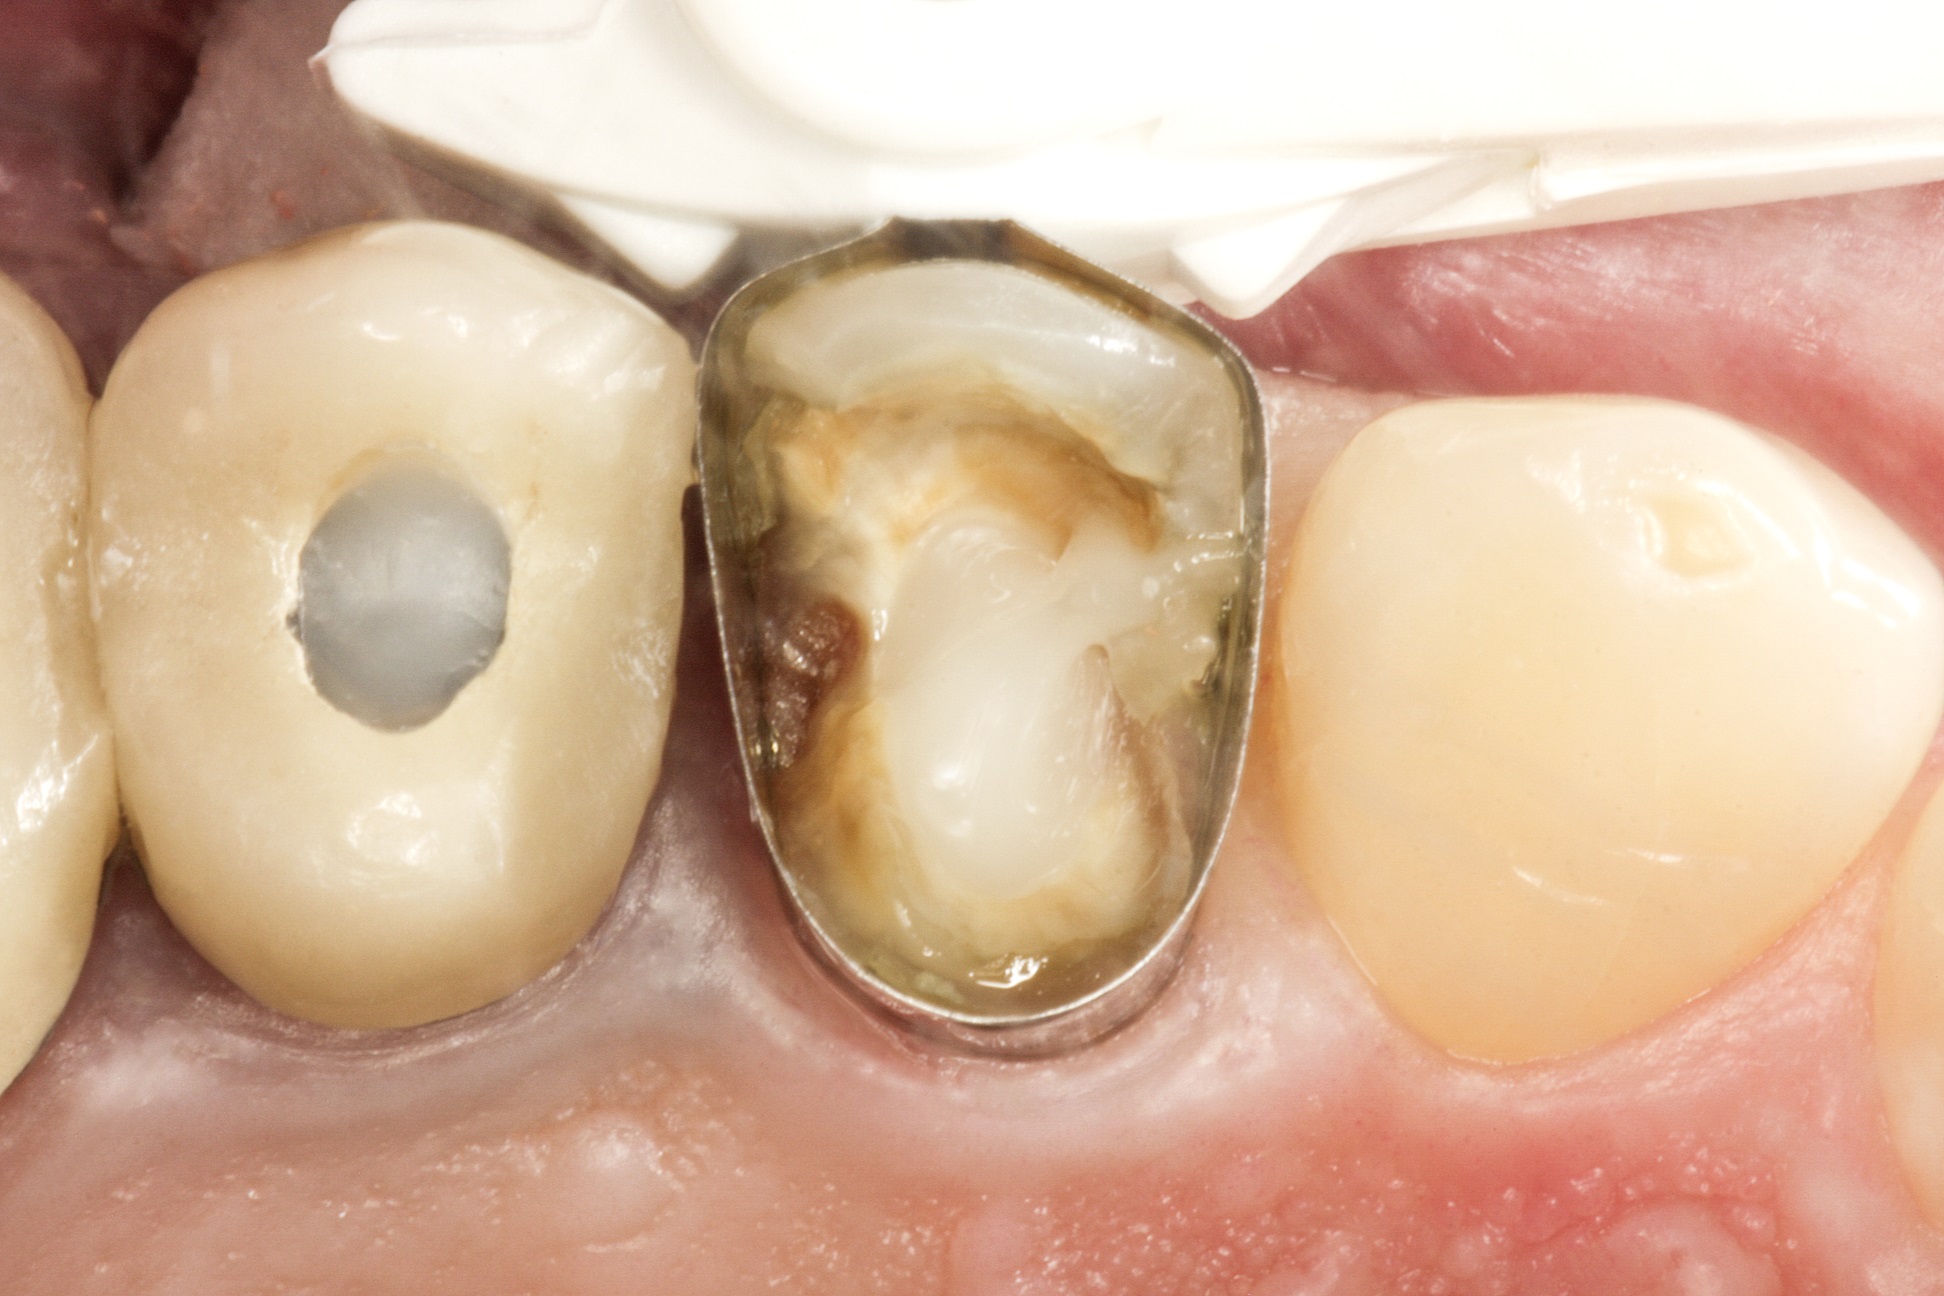

Видаляємо наявну керамічну накладку і невелику зону

каріозного ураження. Знаходимо щічний та язичний канали. За допомогою свердла

для штифтів, що є у комплекті LuxaPost, у кожному каналі створюємо ложе для

штифта глибиною 10-11 мм (рис. 2 і 3).

Фото 2. Кореневі канали після видалення матеріалу для

обтурації.